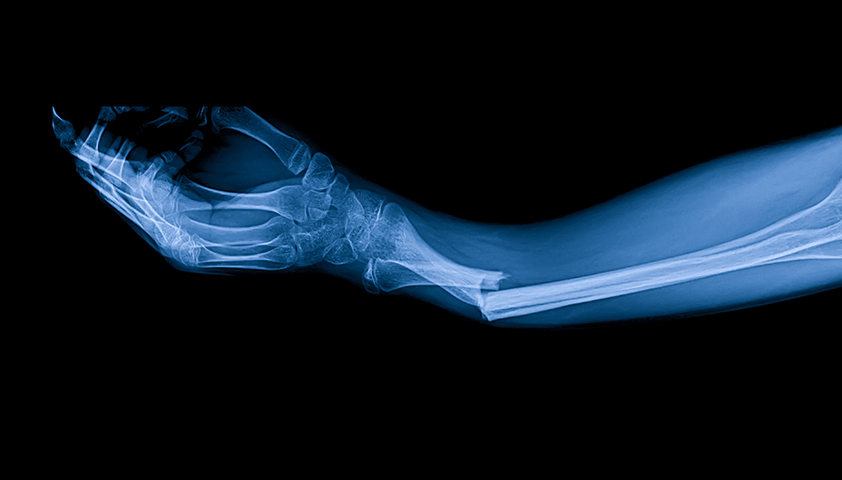

При подозрении на наследственные формы дефицита фосфора исследуют его уровень в моче и проводят генетические тесты. Для оценки состояния костной ткани выполняют денситометрию ДенситометрияМетод диагностики, который используется для измерения плотности костной ткани. и рентгенографию РентгенографияМетод диагностики, который использует рентгеновские лучи для получения изображений внутренних органов, костей и тканей. костей.

Со стороны костно-мышечной системы недостаток минерала может проявляться мышечной слабостью, которая становится особенно заметной при подъёме по лестнице или вставании со стула. Нередко отмечаются боли в костях, а в тяжёлых случаях — деформации костей у детей и патологические переломы у взрослых (переломы, не связанные с травмой).

Кости и мышцы страдают в первую очередь. У взрослых развивается остеомаляция (размягчение костей), а у детей — рахит, который проявляется болями в костях, их повышенной ломкостью и деформацией скелета. При длительной нехватке фосфора мышцы ослабевают: без лечения процесс может привести к полному параличу. Кроме того, острый дефицит минерала может вызвать постепенное разрушение мышечной ткани с возможным развитием острой почечной недостаточности.